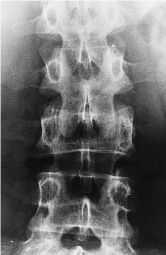

Las radiografíasrealizadas en vértebra L-IV (fig. 2A) y en la TAC (fig. 2B)confirman estas imágenes, apareciendo sobre las lesioneslíticas una imagen de vidrio en polvo, característicade displasia fibrosa.

Figura2A.